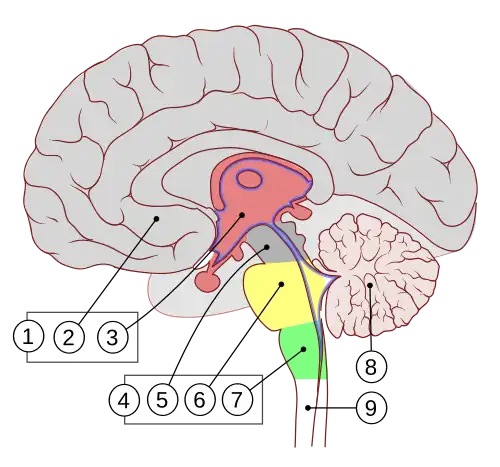

Anatomia

1. Encéfalo frontal

2. Telencéfalo

3. Diencéfalo

4. Tronco cerebral

5. Mesencéfalo

6. Ponte

7. Bulbo raquidiano

8. Cerebelo

9. Medula espinhal

O cérebro, que consiste nos hemisférios cerebrais, forma a maior parte do encéfalo e recobre as outras estruturas cerebrais[6] A região externa dos hemisférios, o córtex cerebral, é a massa cinzenta, consistindo de camadas corticais de neurônios. Cada hemisfério é dividido em quatro lobos principais - o lobo frontal, o lobo parietal, o lobo temporal e o lobo occipital.[7] Três outros lobos são incluídos por algumas fontes, que são um lobo central, um lobo límbico e um lobo insular.[8] O lobo central compreende o giro pré-central e o giro pós-central e está incluído, pois forma um papel funcional distinto.[8][9]

O tronco encefálico, semelhante a um talo, se fixa e deixa o cérebro no início da área do mesencéfalo. O tronco cerebral inclui o mesencéfalo, a ponte e o bulbo raquidiano. Atrás do tronco cerebral está o cerebelo (latim para pequeno cérebro).[6]

O cérebro contém os ventrículos onde o líquido cefalorraquidiano é produzido e circulado. Abaixo do corpo caloso está o septo pelúcido, uma membrana que separa os ventrículos laterais. Abaixo dos ventrículos laterais está o tálamo e na frente e abaixo deste está o hipotálamo, que leva à glândula pituitária. Na parte posterior do tálamo está o tronco cerebral.[25]